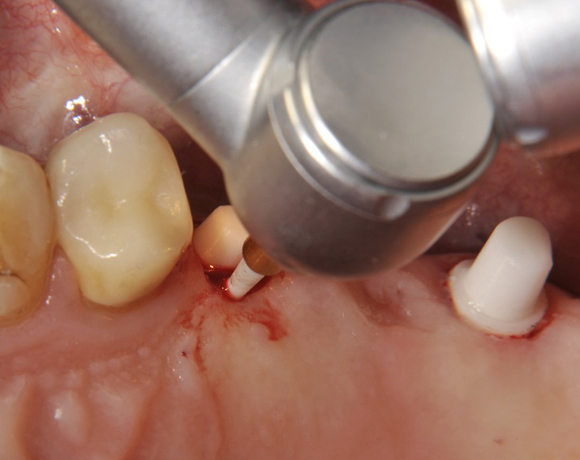

Im vorliegenden Patientenfall wurden für die Zähne 25 und 27 jeweils ein Implantat gesetzt. Nachdem die Implantate eingeheilt waren, wurde 25 – 27 mit einer Brücke versorgt.

Der operative Teil

Der prothetische Teil